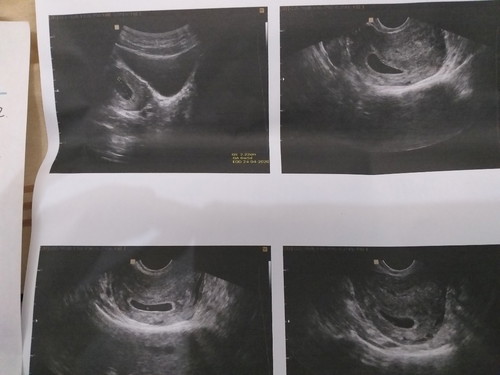

6minggu

Selamat pagi bunda, maaf bun sy hamil pertama. Ini si dedek usia 6mg 5hr. Kata dokter baru ada kantungnya bun. Normal gak ya bun? Makasih bunda❤

Normal bunda